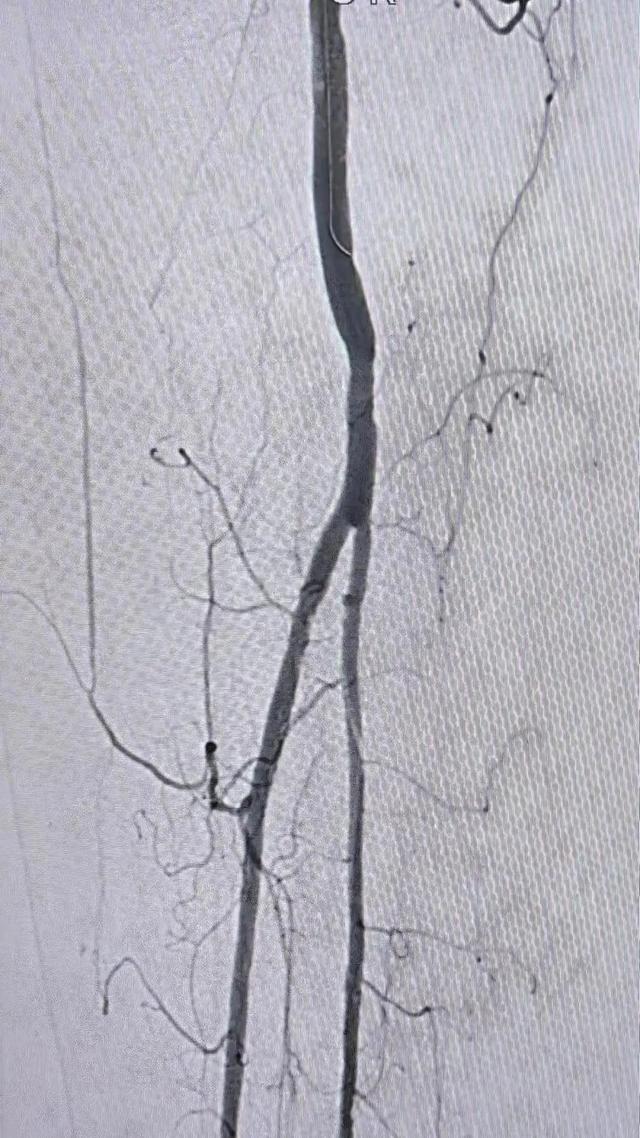

血管外科姜坤主任团队仔细分析患者病情,该患者在动脉硬化闭塞基础上继发血栓形成,且血栓负荷量大,身体状况差,行麻醉及开放手术取栓的风险大,遂制定了微创腔内的手术方案,采用动脉机械血栓清除+血管成形术。

术中选用Rotarex导管行血栓清除,对管腔内残留的血栓放置溶栓导管,最后采用球囊扩张狭窄病变,管腔获得满意。